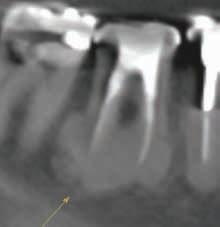

2-Dimensional Radiography

The use of intraoral periapical (PA) and bite-wing radiographs to detect CEJ and alveolar bone levels has been reported.20,21 They also serve as tools aiding in the diagnosis and treatment planning of APE cases.22 Zanatta and colleagues compared the accuracy of PA and bite-wing radiographs and TGP in the planning of crown lengthening procedures with the DBL measurement.23 All methods had statistically significant differences and were inferior in accuracy compared with the reference standard. Measurements obtained via TGP were the closest in accuracy compared with the reference standard, followed by bite-wing radiograph. PA radiographs were the least accurate among the methods investigated.23

Grimard and colleagues reported a strong correlation between CBCT and direct surgical measurements of the hard tissues.27 Although CBCT was found to underestimate the distance from CEJ to the base of bone defect, it precisely estimated the distance between CEJ and alveolar crest. In contrast, intraoral PA radiographs were found to be less reliable than CBCT, as they underestimated the measurements of all investigated parameters considerably.27 Batista and colleagues suggested the use of CBCT for the diagnosis and presurgical planning of APE cases, as it provides accurate measurements related to the CEJ and alveolar bone crest, in addition to the actual anatomic crown length.4